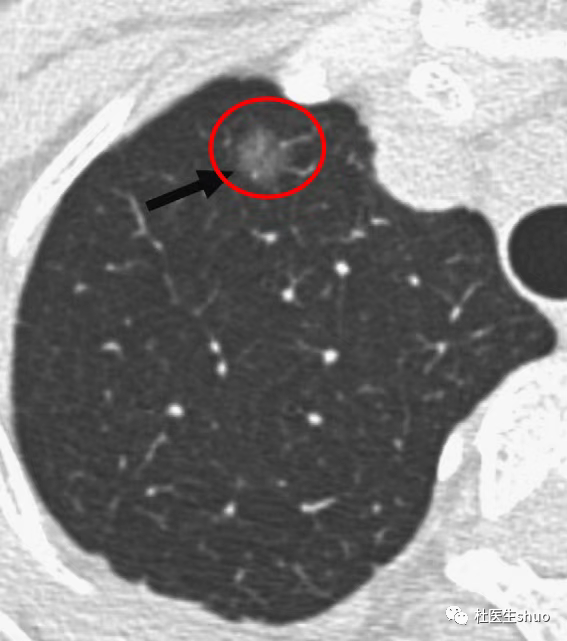

长期且持续存在、实性成分比例增加的肺部磨玻璃结节,这种结节就需要注意了。

从胸部CT上看,肺部磨玻璃结节的影像表现类似磨玻璃,呈现云雾状的圆形、类圆形病灶或不规则阴影。

如果持续复查多次胸部CT,提示结节增大或磨玻璃结节实性比例增加时,可考虑外科手术。